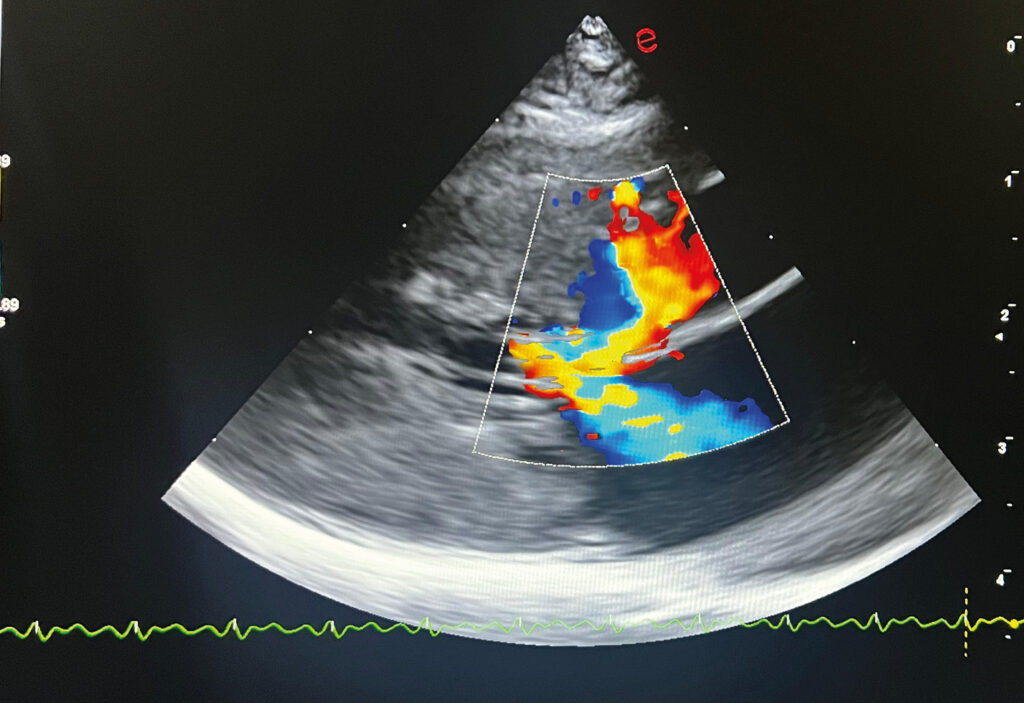

El SAM es el movimiento anormal de la valva anterior de la válvula mitral hacia el septo interventricular durante la sístole, lo que provoca una turbulencia en el flujo de salida del ventrículo izquierdo. Debido a ello, la válvula mitral permanece parcialmente abierta durante esta fase, y se observa una regurgitación mitral. Los dos flujos turbulentos simultáneos son característicos de este fenómeno (imagen 10).

Imagen 10. A) Diagrama de la obstrucción del tracto de salida del ventrículo izquierdo resultante del movimiento sistólico anterior (SAM) de la valva anterior de la válvula mitral (flecha). AI: aurícula izquierda; LV: ventrículo izquierdo; Ao: aorta. B) Ecocardiografía vista paraesternal derecha eje largo, con Doppler color, presencia de SAM. El movimiento anormal de la valva anterior de la válvula mitral hacia el tabique interventricular en la sístole temprana provoca interferencia dinámica del flujo de salida del ventrículo izquierdo y turbulencia en el tracto de salida. Dado que la válvula mitral permanece parcialmente abierta durante esta fase, también se observa insuficiencia mitral. Los dos flujos turbulentos simultáneos son característicos de este fenómeno.